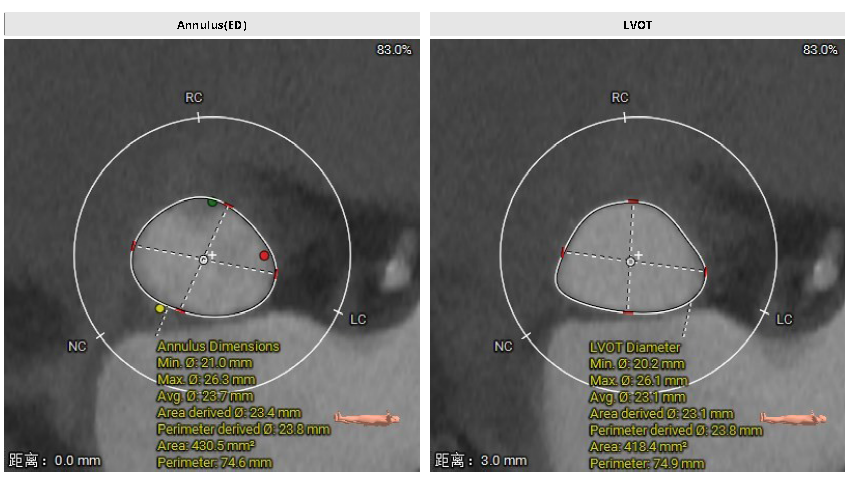

术前CT评估

主动脉根部分析:Type1型二叶瓣,L-R融合,瓣叶明显增厚,轻度钙化,钙化积分196mm³(HU850),主要分布于瓣叶、瓣叶根部。舒张期瓣环面积430.5mm²,折合内径23.4mm。

左心评估:左室扩张,室间隔增厚,心尖变薄。瓣环水平夹角68°,提示横位心。